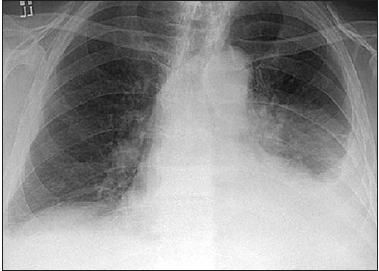

The results of the laboratory workup were significant only for a white blood cell (WBC) count of 17.8 × 103/μL, with 91% neutrophils. Stool samples were negative for Clostridium difficile toxin. A chest radiograph obtained on admission demonstrated a moderate left-sided pleural effusion (Figure 2).

Figure 2 – A chest radiograph obtained on admission demonstrated a moderate left-sided pleural effusion.